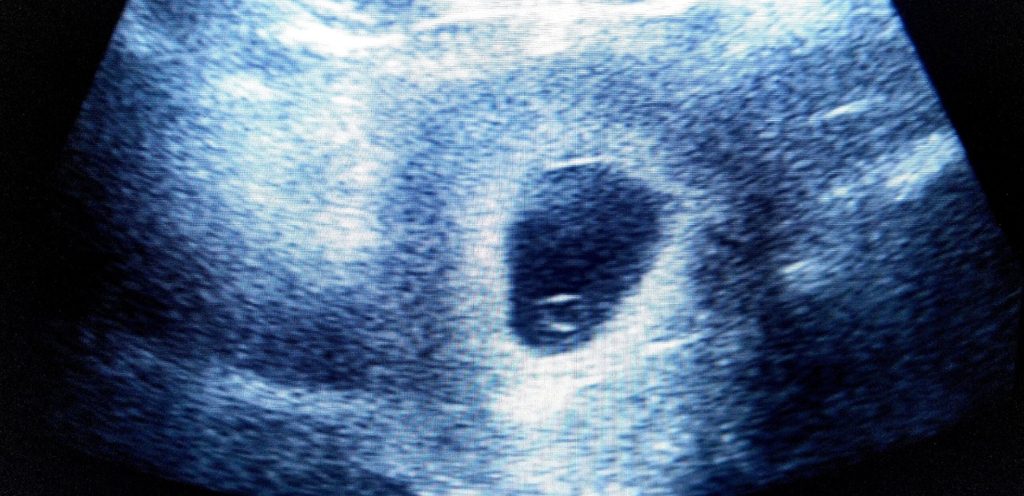

لا يزال الحمل لمدة 5 أسابيع مبكرًا جدًّا مع بدء تكوين طفلك. قد يظهر فحص الموجات فوق الصوتية عبر المهبل في الحمل لمدة 5 أسابيع كيسًا صغيرًا يبلغ حجمه حوالي 5 مم في بطانة الرحم (الرحم). حول كيس الحمل يوجد شريط أبيض سميك من الأنسجة يسمى المشيمية. هذه هي المشيمة المستقبلية.

كيس الصفار هو الهيكل الأول الذي يتطور داخل كيس الحمل. يلعب دورًا مهمًا في نمو طفلك ويوفر العناصر الغذائية اللازمة في الجزء الأول من الحمل. على الموجات فوق الصوتية، يبدو كيس الصفار مثل فقاعة داخل كيس الحمل. نظرًا لأنه مهم جدًا للنمو المبكر للطفل، فهو هيكل مهم لفريق رعاية الموجات فوق الصوتية لرؤيته ويمكن أن يساعد أيضا في تشخيص ما إذا كان الحمل صحيًا، أو حدث الإجهاض.

- المرحلة الثانية: عادة ما يكون هذا بعد أربعة إلى خمسة أسابيع من الدورة الشهرية الأخيرة للمرأة الحامل. تظهر الموجات فوق الصوتية عادة مجموعة صغيرة من السوائل داخل بطانة الرحم التي تمثل التطور المبكر لكيس الحمل.

- المرحلة الثالثة: عادة ما يكون هذا بعد حوالي خمسة أسابيع ونصف من الدورة الشهرية الأخيرة للمرأة الحامل. عادة ما تظهر الموجات فوق الصوتية كيس الحمل وداخله يمكننا أن نرى بنية تشبه الفقاعة 3-5 مم، وهي كيس صفار البيض.